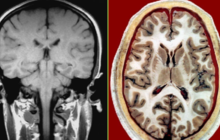

人体机能与健康

人体断层影像解剖学